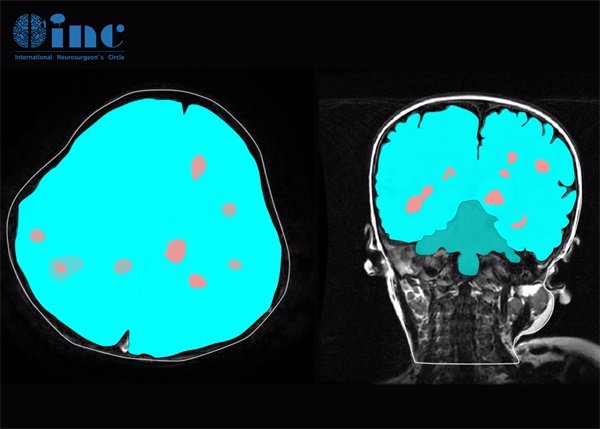

脑海绵状血管瘤在CT影像上可以呈现出一系列特殊的表现,这些表现对明确诊断具有重要的现实意义。通常情况下,CT扫描可显示出特定的结构和形态变化。

最为人们熟知的影像特点是低密度区。在CT扫描中,脑海绵状血管瘤常表现为明显的低密度影,通常因为其含有丰富的血管成分,这种低密度影在增强扫描中也不易改变。低密度区的大小及形状在不同患者中可能有所不同,但一般呈现椭圆形或不规则形状。

脑海绵状血管瘤常伴有周围水肿的现象,这在CT影像中表现为低密度带。这种水肿可以是由于血管瘤的生长所致,从而影响到周围脑组织。部分患者可能在水肿象限周围有明显的中线移位,这对于医生在诊断过程中的判断尤为重要。